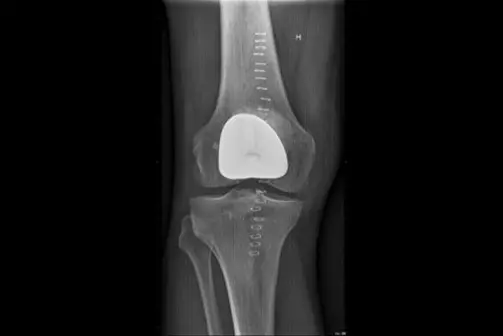

Ei kneprotese, erstattar dei øydelagde leddflatene. Det finnast ulike typar proteser som vert nytta, avhengig av graden av slitasje i kneet.

Kneprotesen er ein erstatning for øydelagde leddflater i kneet. Den består av 2 metalldelar som vert festa på lårbeinet og skinnebeinet. Leddflata på lårbeinet består av metall, leddflata på skinnebeinet av høgforedla plast. Metalldelane vert festa med eller utan beinsement. Ei totalprotese dekkjer heile leddflata både på lårbeinet og på skinnebeinet. Det pre- og postoperative forløpet er likt for alle protesetypane.